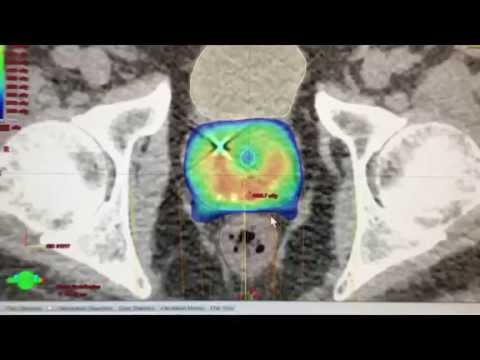

what's proton therapy chicago most cancers care. Proton therapy goals tumors with precision. Proton therapy is an effective shape of radiation remedy for many types of tumors. It destroys most cancers cells with the aid of. Prostate cancer radiation therapy webmd. Oct 21, 2017 webmd explains the usage of radiation therapy for prostate most cancers, inclusive of internal and outside radiation remedy, how radiation therapy is performed. Degree i prostate most cancers texas oncology. Stage i prostate most cancers. Review. Prostate most cancers is referred to as level i if it cannot be felt in a physical exam and there may be no evidence that cancer has. Fiveyear outcomes from 3 prospective trials of photograph. Motive. To file 5year clinical results of three prospective trials of imageguided proton remedy for prostate most cancers. Prostate cancer survivors remedy choices. It'd be very unusual for chemotherapy for use as a number one therapy for early degree prostate cancer, the maximum typically recognized form of the disease.

Advanced cancer treatment with proton therapy. As one of 25 therapy centers in the u.S., California protons cancer therapy center in san diego is at the forefront of cancer innovation and technology.

Radiation remedy wikipedia. Radiation therapy or radiotherapy, often abbreviated rt, rtx, or xrt, is remedy the usage of ionizing radiation, normally as a part of cancer treatment to control or kill. What is proton remedy chicago most cancers care. Proton remedy targets tumors with precision. Proton therapy is an powerful form of radiation therapy for plenty forms of tumors. It destroys most cancers cells via. Prostate cancer radiation remedy webmd. · webmd explains the usage of radiation remedy for prostate cancer, including inner and external radiation remedy, how radiation remedy is performed. Proton remedy vs radiation updated information 7 days a week. Incredible & useful information with us. Get proton therapy vs radiation consequences here! Prostate cancer proton remedy center. With proton therapy, you could beat prostate most cancers without compromising your great of existence. Proton remedy is an powerful treatment for prostate cancer and has. Advanced cancer remedy with proton remedy california. As one in every of 25 therapy centers inside the u.S., California protons most cancers remedy middle in san diego is at the leading edge of most cancers innovation and era.